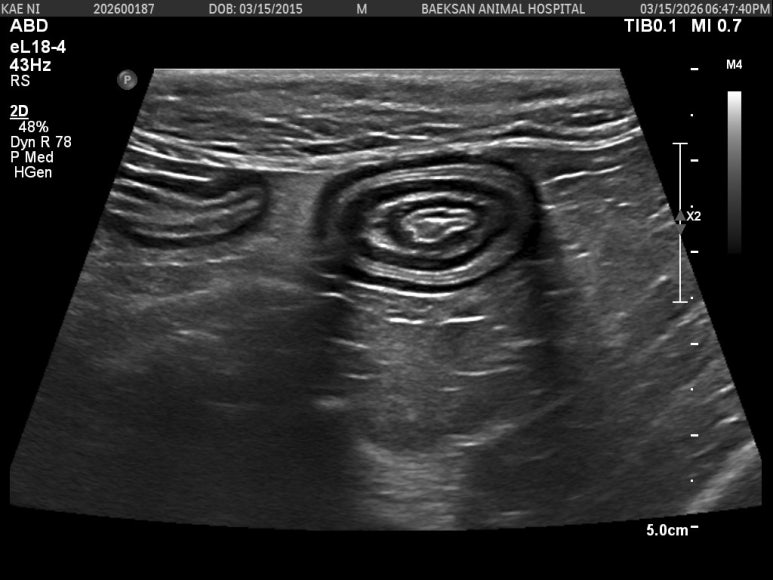

수혈을 진행하며 아이의 호흡과 바이탈을 안정시키는 동시에, 도대체 왜 이렇게 빈혈이 심하고 밥을 못 먹었는지 원인을 찾기 위해 정밀 복부 초음파 검사를 진행했습니다.

▲ 화면 중앙에 마치 과녁판이나 양파 단면처럼 동심원을 그리는 뚜렷한 형태가 보이시나요? 이는 장의 한 부분이 연결된 다른 장의 내강으로 말려 들어가는 장중첩상태를 나타냅니다.

이렇게 장이 겹쳐서 막히게 되면 극심한 통증이 발생하고 음식물이 지나갈 수 없으며, 혈액 공급이 차단되어 장조직이 괴사하기 시작합니다. 이는 발견 즉시 중첩된 장을 원래대로 환원하거나 절제해야 하는 응급 수술 상황입니다.